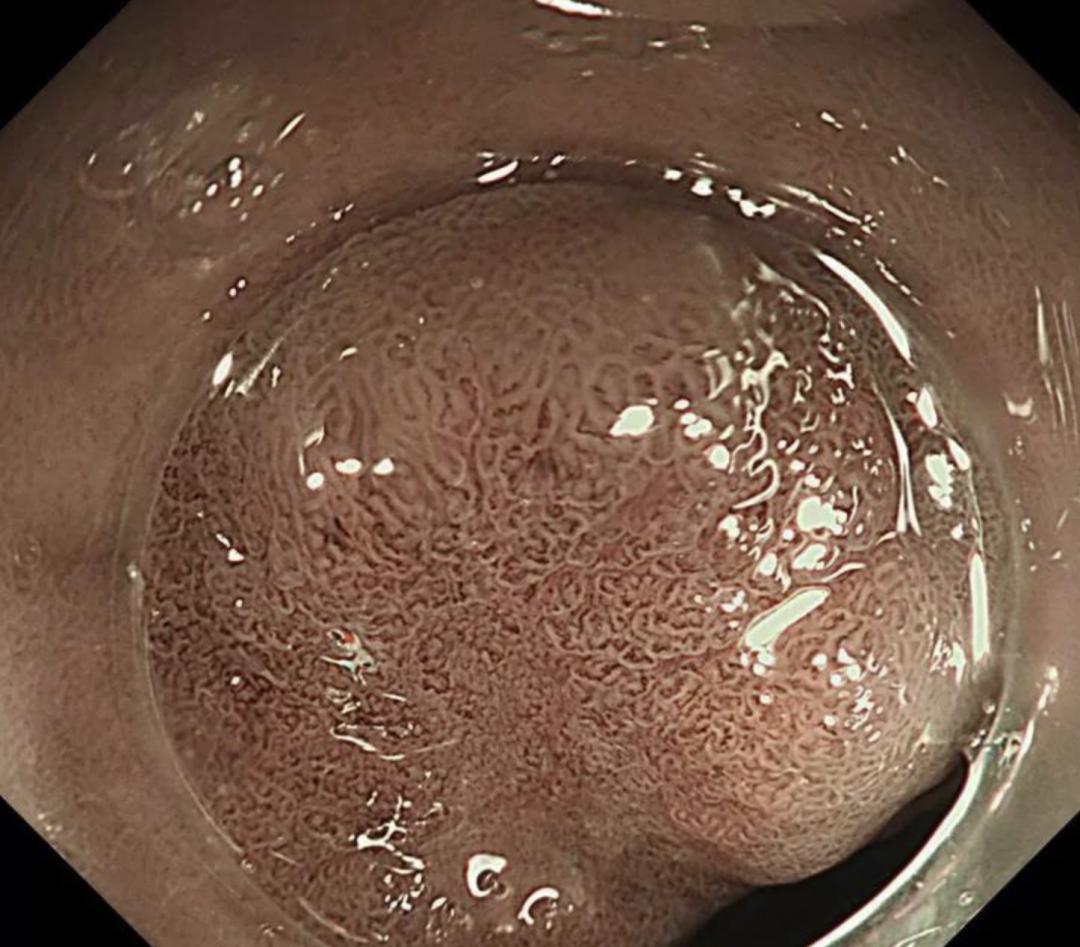

胃溃疡是极为常见的一种疾病,好发部位在胃角、胃窦、贲门和幽门管等部位,多见于中老年朋友。

胃从内到外分胃腔、黏膜层、黏膜肌层、黏膜下层、固有肌层、浆膜层。如果黏膜损伤只有黏膜层的缺损,比较浅,通常认为是胃糜烂。

如果缺损超过黏膜肌层,损伤深度达到了黏膜下层,甚至可以达到固有肌层,就诊断为胃溃疡。典型的胃溃疡疼痛是很有规律的,一般在吃完东西以后半个小时或者一个小时开始发生上腹部的疼痛,疼痛持续几个小时,有灼烧感,随后疼痛缓解,直到下一次进食后疼痛又开始。

当溃疡严重时,黏膜缺损的深度突破浆膜层时,就会发生胃穿孔。无论是糜烂还是溃疡,当损伤到血管的时候,可以引起血管的破裂,导致出血、呕血或者黑便,即所谓的上消化道出血。

如果胃溃疡没有得到良好的治疗有可能进展成胃癌,虽然总体来说这种概率不是特别高,但是患了胃溃疡还是应该高度警惕,因为在“溃疡家族中”,它是和癌症离得最近的疾病。特别是胃溃疡反复发作,并伴有比较严重的症状,比如大便呈亮黑色、有出血时,建议尽快去医院做检查。